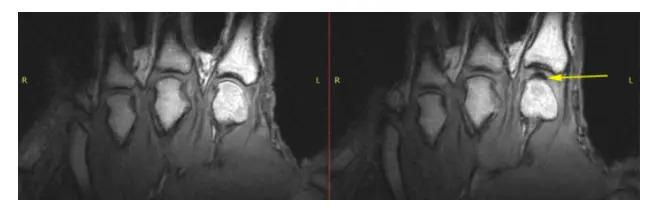

然而一个加拿大的研究团队却认为:咔咔声不是气泡破裂声,而是形成时候的声音。

为此他们动用了核磁共振扫描仪,对掰扯的关节进行可视化的观察。

图片来源:PLoS ONE

当手指关节被拉伸时,关节腔中确实产生了一个黑色的气体空腔。但在听到咔的一声后,气体空腔仍然存在。

如果是破裂产生的声音,那么空腔应该消失不见。

不过,这个结论并不被大家接受,研究者也承认技术所限,这个空腔可能是气泡破裂后残余的。